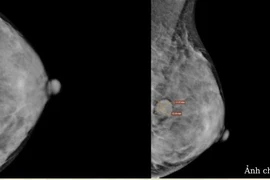

Ung thư vú là nguyên nhân gây tử vong hàng đầu trong các loại ung thư ở phụ nữ trên thế giới. Tuy nhiên, có một số nhóm người có nguy cơ cao mắc ung thư vú.